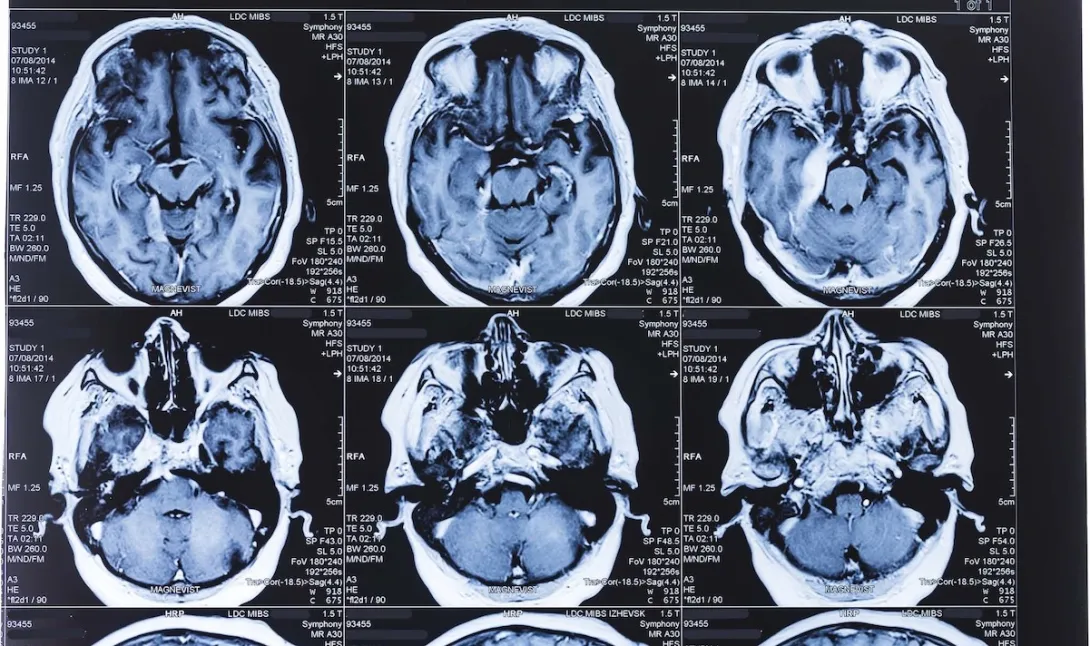

Viz.ai built a care-coordination tool designed to help clinical teams share images and detect potential diseases. The product's AI tool is able to help triage the clinical images and detect strokes, and in turn help care teams prioritize patients. Currently its offering includes AI detection productions for aortic diseases, pulmonary embolism and cerebral aneurysms. The company noted that it has a pending 510(k) clearance for subdural hematoma.

Specialists using the system are able to access a mobile view of scans, which allows them to zoom in and out of images and visualize the scan in 3D.